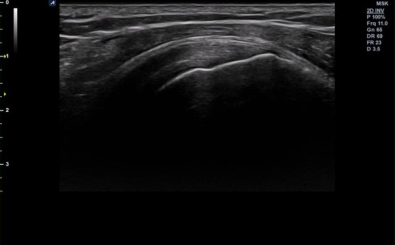

CLINICAL IMAGES

臨床影像

Shoulder